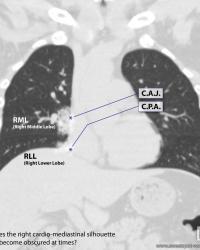

Enhanced coronal CT reconstruction |

Obscured Sweet Spot™ Landmarks |